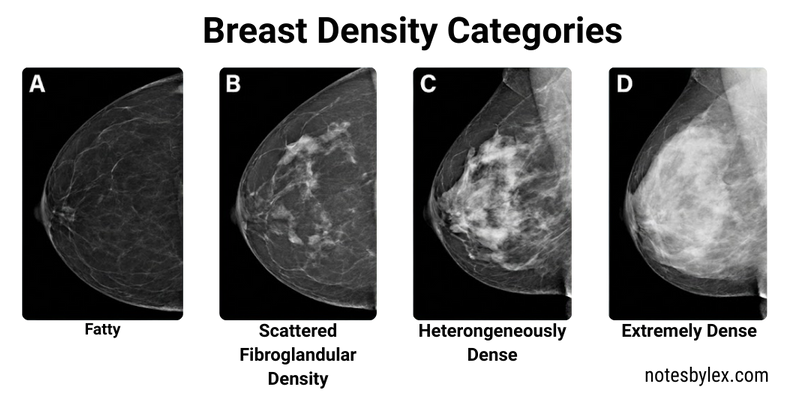

Radiologists also classify breast composition by density using four categories:

- A - almost entirely fatty

- B - scattered fibroglandular densities

- C - heterogeneously dense

- D - extremely dense

Higher breast density both increases breast cancer risk and reduces mammographic sensitivity, as dense tissue appears white on mammograms (the same appearance as potential tumours), effectively masking lesions.